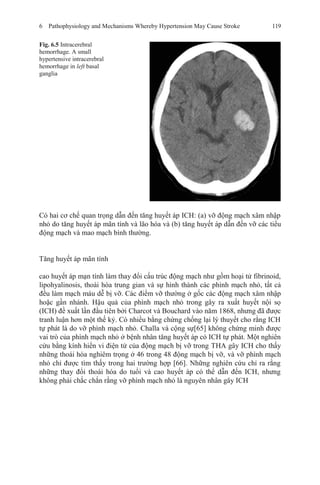

18. Kuramoto K, Matsushita S, Kuwajima I, Murakami M. Prospective study on the treatment of

mild hypertension in the aged. Jpn Heart J. 1981;22:75–85.

19. Hypertension Detection and Follow-up Program Cooperative Group. Five-year findings of the

Hypertension Detection and Follow-up Program: III. Reduction in stroke incidence among